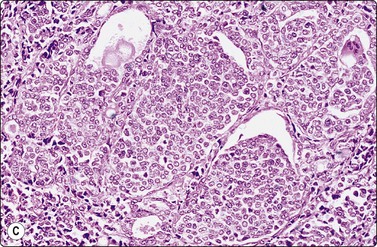

FNs are classified as benign (FA) and malignant (FC). FAs and most FCs are encapsulated tumors, occurring in one of the lobes. Histological diagnosis of a well-differentiated FC requires demonstration of capsular and/or vascular permeation. Most FNs, especially adenomas, have a uniform internal structure that is reflected in the cytological smears. FAs are more common in women and microscopically show a variety of histological patterns such as microfollicular (fetal), normofollicular, macrofollicular, trabecular, solid (embryonal), Hurthle cell and atypical adenomas.42 Cytologically, follicular lesions include FA, FC, cellular NG and FV-PC.121

Smears in FN are cellular in a bloody background that is usually devoid of colloid. Many uniform-sized follicular cell clusters, microfollicles and rosette formations are present. Syncytial aggregates, nuclear crowding and overlapping are also often seen.

The repetitive smear pattern with uniform cell population is in contrast to the variable pattern of different cell types seen in colloid and hyperplastic nodules. Microacinar clusters with a central lumen (that may contain a drop of colloid) represent microfollicles (Figs 6.18, 6.19 and 6.21B). These are characteristic of FN but may be found focally in NG. Rosette-like groupings without a lumen (Fig. 6.20) suggest a more solid growth pattern. A trabecular pattern is represented by rows and elongated aggregates of epithelial cells that resemble papillary structures when they adhere to strands of vascular stroma (see Fig. 6.33B,C). Small blood vessels with adherent epithelial cells can be found in any type of follicular neoplasm (see Fig. 6.25A).

The distinction between FN and NG is the most common differential diagnostic problem in solitary nodules as cytological appearances overlap (Fig. 6.22). A microfollicular focus in a colloid nodule cytologically resembles a microfollicular neoplasm, while smears from a macrofollicular (colloid) adenoma resemble a dominant nodule in multinodular goiter. Jaffar122 indicated that the presence of hemosiderin within macrophages and follicular cells excludes FN. The false-negative rate of cytology in FN may be 30% or more because of the inability to recognize normofollicular neoplasms.123 However, these distinctions are of little clinical importance as long as the nodule is recognized as benign and spared from unnecessary surgery.

Most FCs are microfollicular, trabecular or solid, contain little colloid, and will be reported as ‘FN’ by cytology. Although the failure to recognize FC as neoplastic has been surprisingly high in some series,7 other studies show high diagnostic sensitivity, with false-negative rates as low as 0–2%.11,13,28

Cytological features in FA and FC are similar, with cellular smears composed of syncytial clusters of crowded cells. There is a tendency for uniform nuclear enlargement in FC, whereas FA may show small or large nuclei.124 These differences are often subtle, with much overlapping (Fig. 6.20).3,68,125 Cells from a well-differentiated but clinically aggressive FC may not appear obviously atypical or enlarged in smears (Figs 6.23, 6.24B). Anisokaryosis per se is more a feature of non-neoplastic lesions such as NG and thyroiditis.42